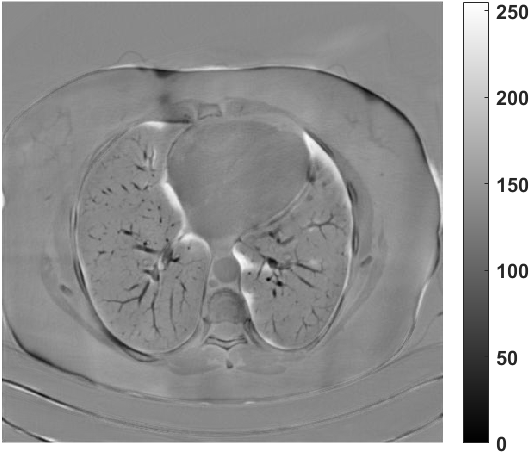

We further increase the noise level contained in the raw data to 10% white Gaussian noises and list the quantitative results in Table IV. It can be observed that the reconstruction performance of the TV model is poor in the case of high-level noises with PSNR dropping by 4 to 5 dB compared to the previous experiments. On the other hand, the performance of the learning-based methods is less sensitive to noises. The SIPID method relying on the sinogram interpolation works better than FBP-Unet. And the deep unrolling methods (i.e., PD-net, IFSR-net, SFSR-net) outperform the traditional iterative algorithm when the scanning range is limited and data is corrupted by noises. Similar to the previous experiments, compared with other deep learning algorithms, our LRIP-nets give the reconstruction results with higher PSNR and SSIM. Moreover, the low-resolution image obtained by the projection data down-sampled with rate 1/8 always gives the best reconstruction results with more than 2 dB PSNR and 0.05 SSIM increments compared to the PD-net. Fig. 6 illustrates the reconstructed images from different methodologies with scanning angular range of and 10% Gaussian noises. It can be seen that the both TV model and the FBP-Unet suffers from significant artifacts, which present distortions in the angular range of the missing scan. Other learning-based methods provides better visual qualities than FBP-Unet, and our LRIP-net1/8 still gives the best reconstruction result with correct boundaries and fine structures.

Fig. 7 manifests the reconstruction results of these methods with scanning angular of . It can be seen that both FBP and FBP-Unet produce serious artifacts within the range of missing angles. The TV model performs well in removing Poisson noises, but it can not handle the artifacts very well. Similarly, there left obvious artifacts on boundaries and different degrees of missing in visceral tissues of the reconstruction images obtained by the SIPID, PD-net and FSR-net. The visceral tissue and boundaries of our LRIP-net reconstructions are more intact and smoother, especially for the LRIP-net1/8 which gives the ideal boundaries. The observation becomes even apparent if we look at the zoom-in regions, where the LRIP-nets can produce results with fine structures. Therefore, we conclude that the low-resolution image prior can effectively improve the qualities of the limited-angle CT reconstruction.